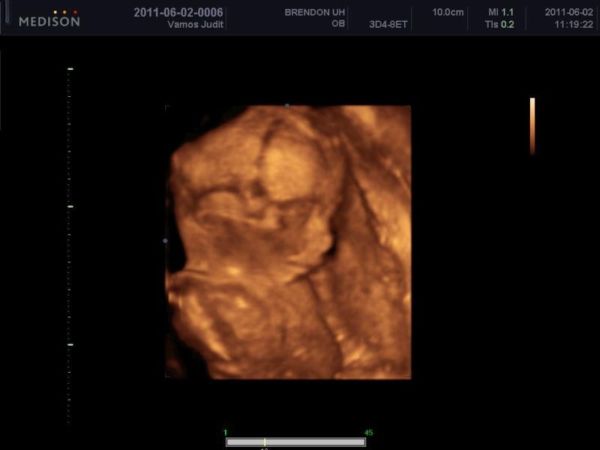

4D, mi voltunk a 16. héten ugye, az nagyon jó volt

csak kicsit hosszú, 30 perc... (élveztem, csak a hasam keményedett be...) elvileg a 25. héten megyünk újra, meg a 30. hetit is 4D-ben kértük... nagyon rossz, a barátnőknek mindig átkapcsol a doki pár percre 4D-be a sima vizsgálatnál, nekünk soha, pedig az a gép is tudná